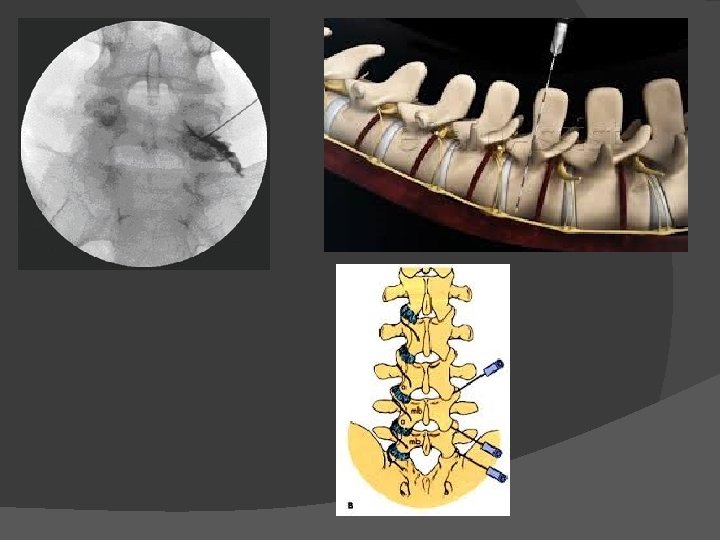

Facet block

Dorsal root ganglion block/ neurolysis

SI Joint Block

Genicular neurolysis